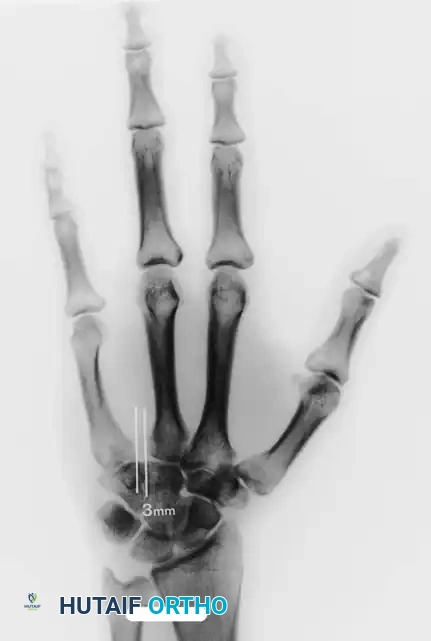

- Insert a Kirschner wire (K-wire) longitudinally through the metacarpophalangeal (MCP) joint of the transposed index ray. Drive it retrograde out the dorsum of the flexed wrist, then advance it proximally through the metacarpal until its distal tip is just proximal to the MCP joint articular surface.

- With the wrist flexed, cut the proximal end of the wire and allow it to retract beneath the skin.

- Critical Step: Flex all remaining fingers simultaneously into the palm. This is mandatory to ensure correct rotational alignment of the transposed ray. The digits must point toward the scaphoid tubercle without overlapping.

- Once rotation is confirmed, insert a second K-wire transversely through the necks of the fourth and the transposed second metacarpals to lock the rotation.

- Alternative Fixation: Bony fixation with a small dynamic compression plate (DCP) or locking plate and screws can be utilized. This requires precise technique. Attaching the plate to the distal fragment first, fully flexing the MCP joints to confirm rotation, and then securing the proximal plate fixation significantly reduces the risk of malrotation.